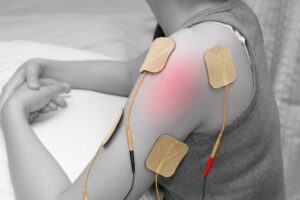

در فیزیوتراپی لگن از تکنیکهاى متنوعى استفاده مىشود. درمانهاى دستى مانند مانیپولاسیون و موبیلزاسیون مىتوانند خشکى مفصل را کاهش دهند. الکتروتراپى، لیزر درمانى و اولتراسوند نیز براى کنترل درد و التهاب به کار مىروند.

کلینیک فیزیوتراپى خانه سلامت به مجهزترین دستگاههاى روز دنیا تجهیز شده است. دستگاههاى لیزر پرتوان، الکتروتراپى پیشرفته، تراپىتیبل و سیستمهاى ارزیابى حرکت دقیق در این مرکز استفاده مىشوند. این تجهیزات امکان درمان هدفمندتر و سریعتر را فراهم مىکنند.